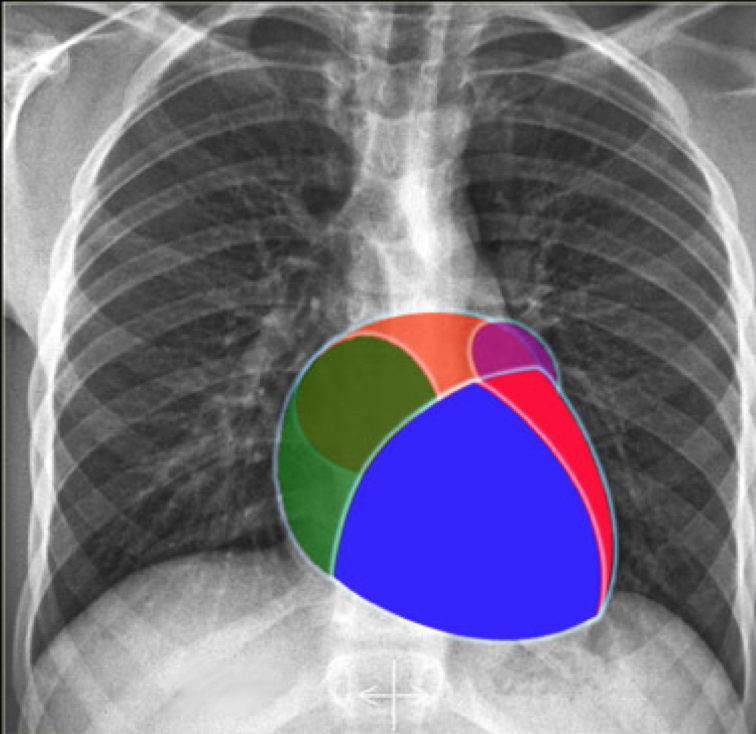

Label the heart chambers